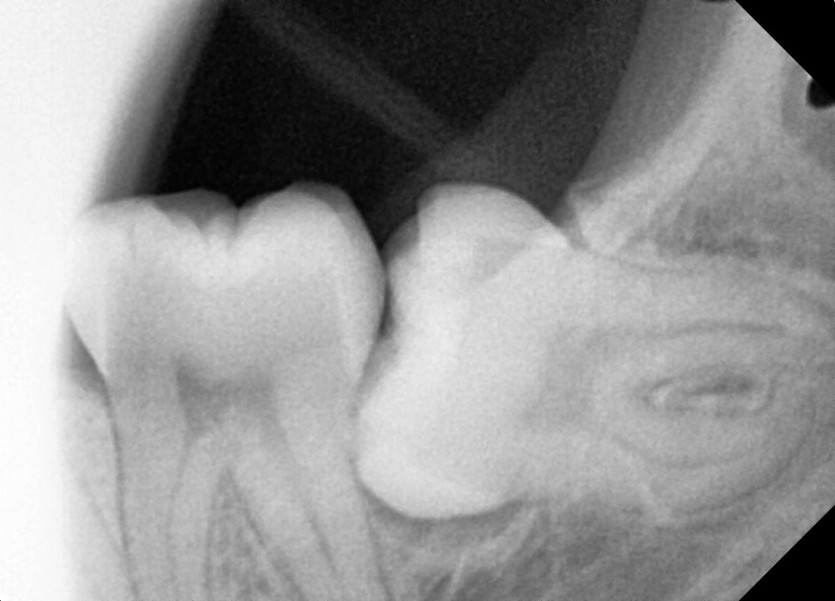

#38 사랑니 발치

구강 외과 전문의가 당일 발치했습니다.